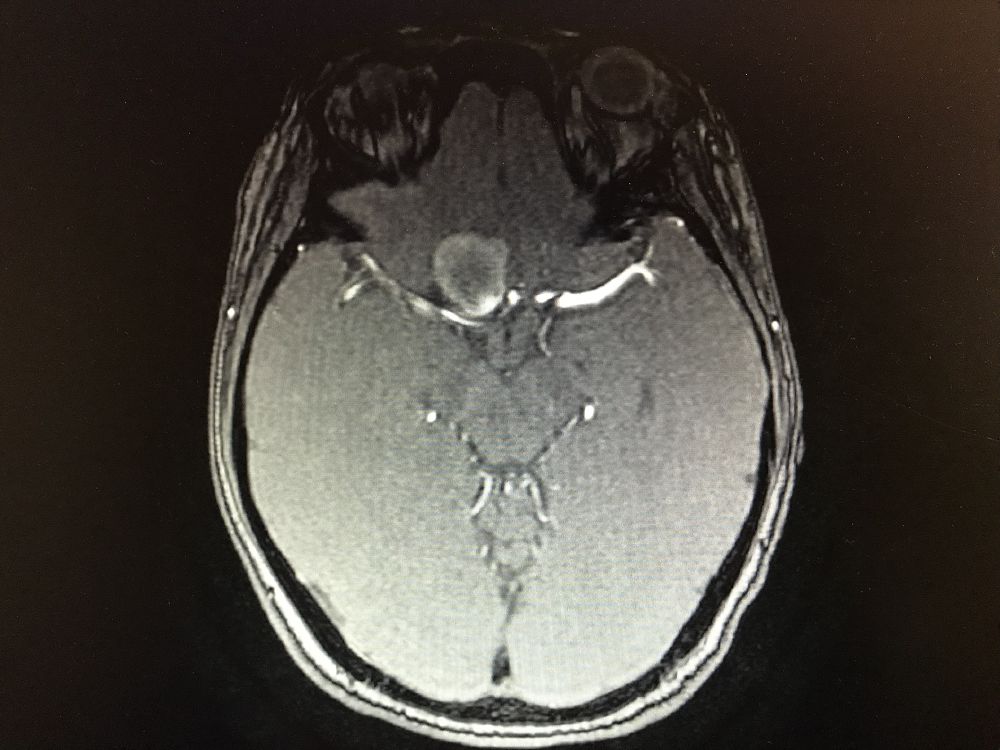

入院后完善DSA检查提示颅内多发动脉瘤:右侧颈内动脉眼段大动脉瘤(约18*19mm,瘤颈6.6mm),左侧眼动脉段及床突段动脉瘤。和家属沟通病情,告知介入和开颅手术风险利弊后,患者家属选择开颅动脉瘤夹闭手术治疗。进一步行DSA+CT融合,模拟手术入路视角。

术前MRA和CTA

右侧眼动脉瘤